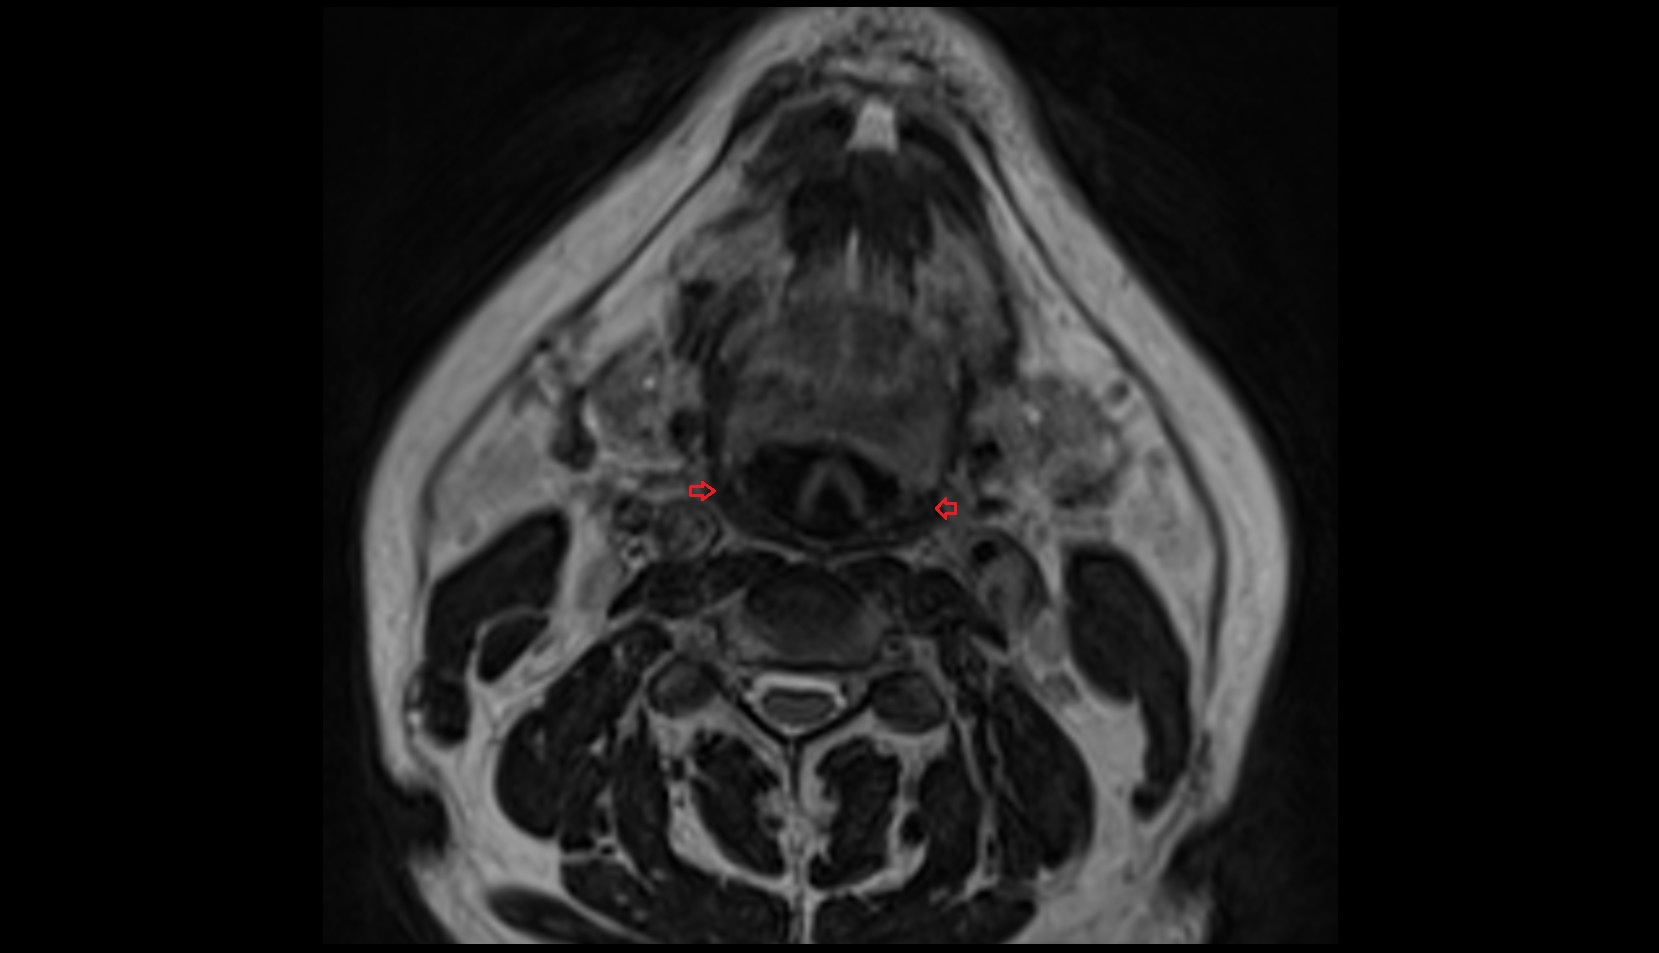

- Temporomandibular joint

- Mandibular condyle

- Mandibular fossa

- Superior head of lateral pterygoid muscle

- Inferior head of lateral pterygoid muscle

- Lateral pterygoid muscle